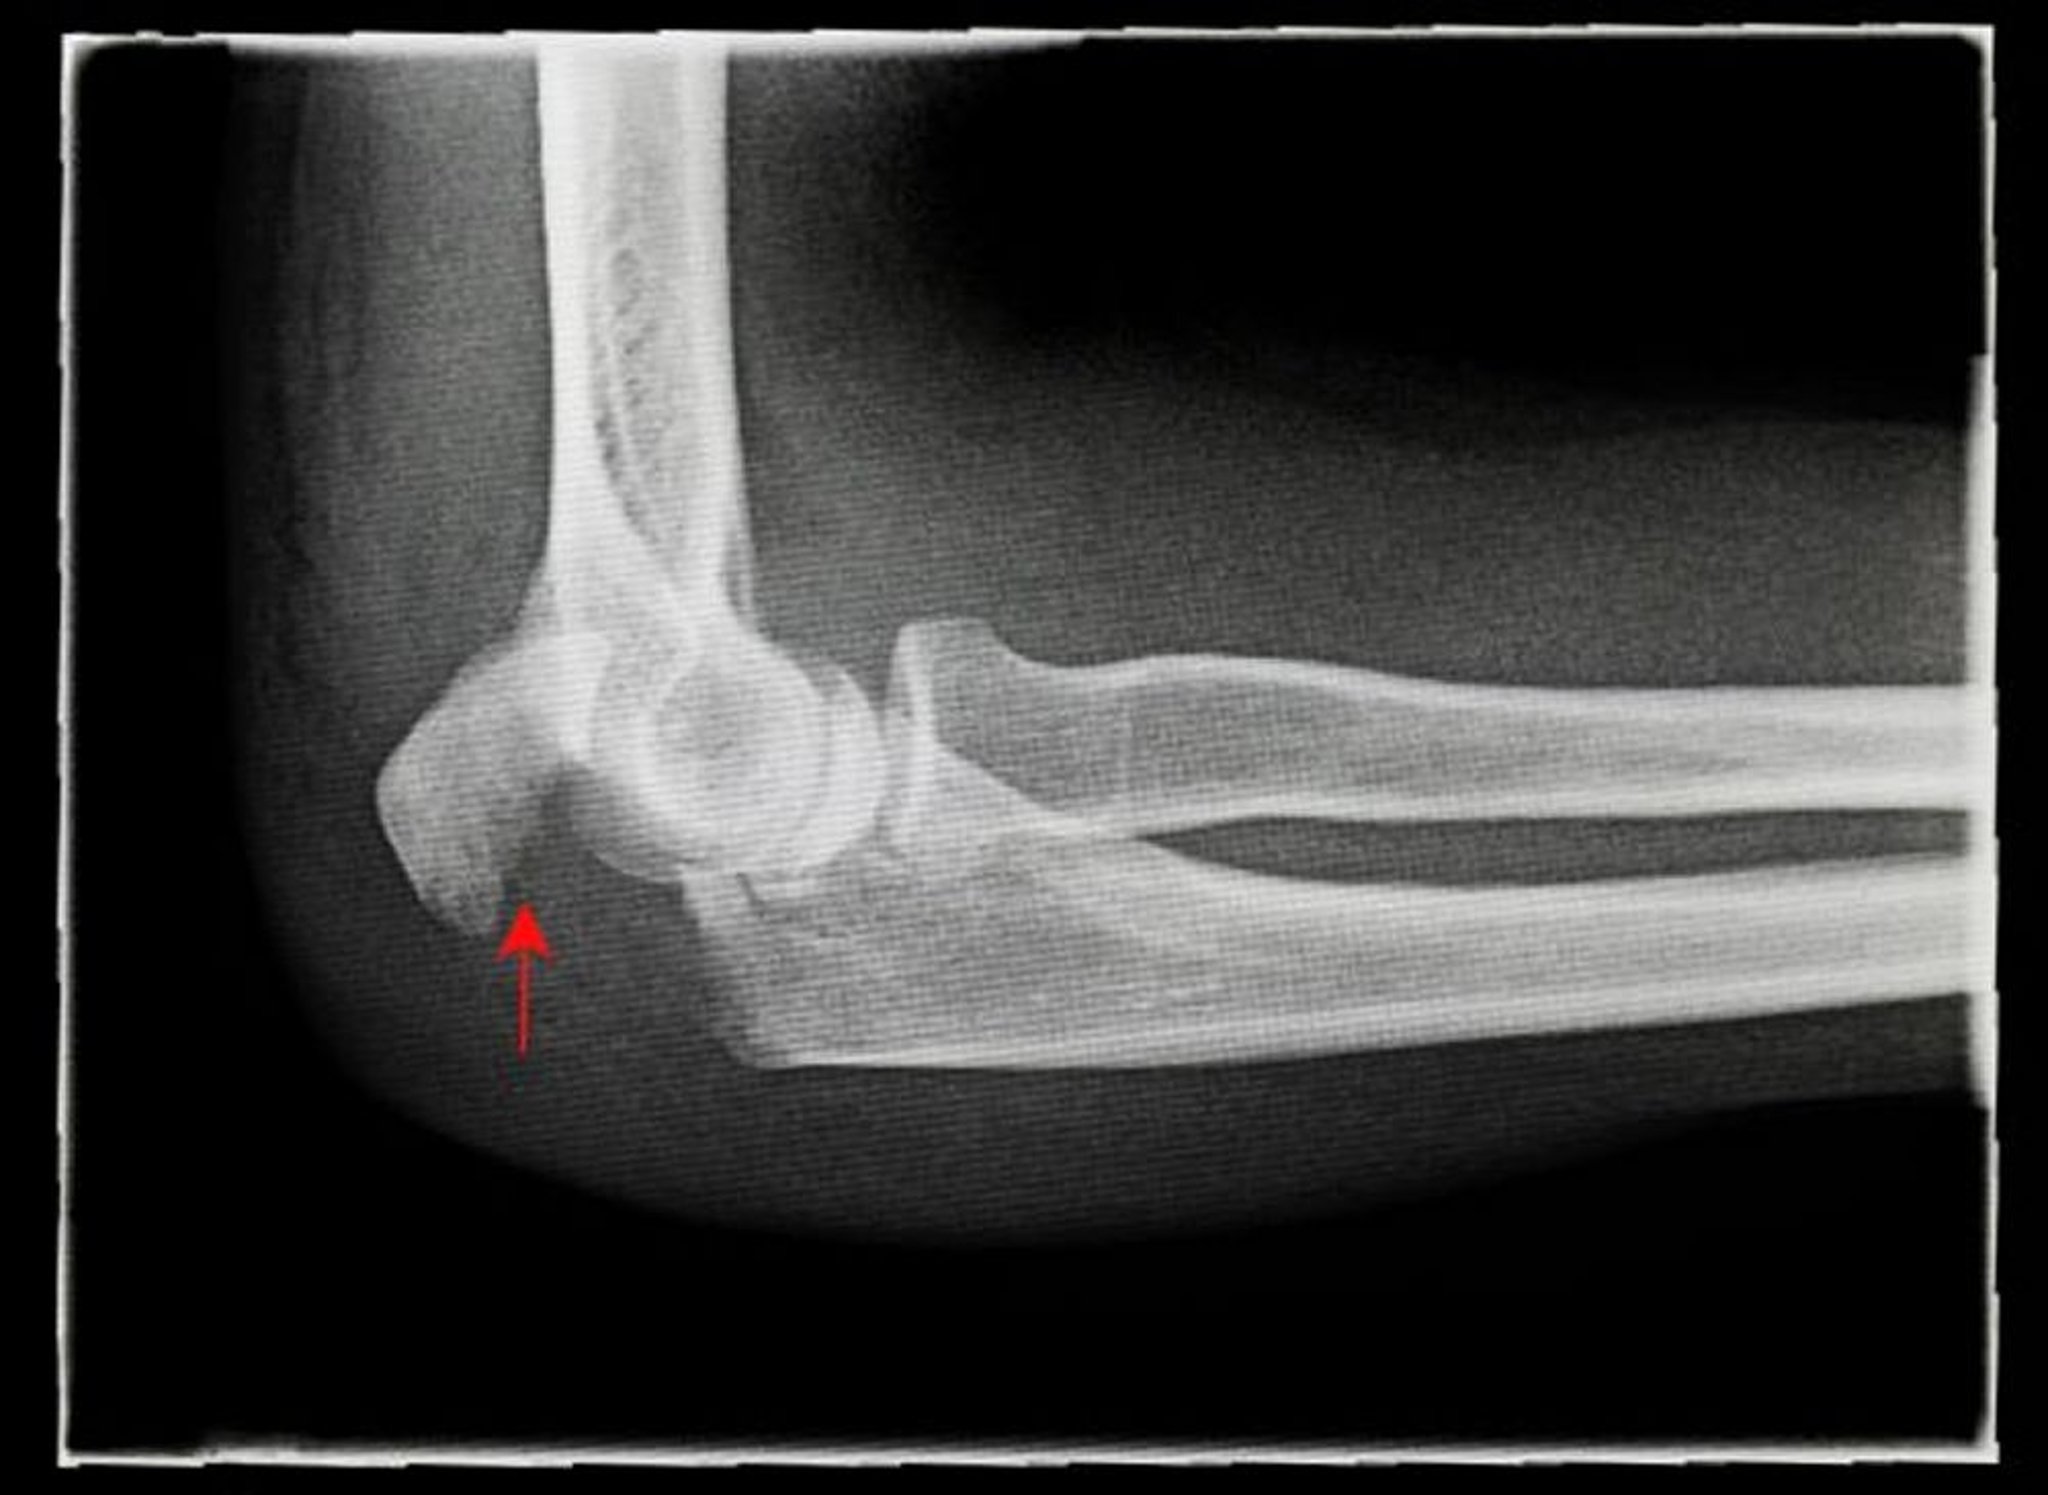

Gãy mỏm khuỷu

Phim chụp X-quang bên này cho thấy một vết nứt ở mỏm khuỷu bị di lệch (mũi tên).